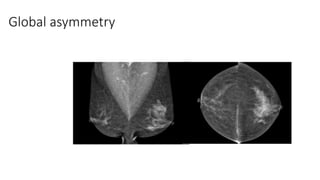

• Global asymmetry consisting of an asymmetry over at least one quarter of the

breast and is usually a normal variant.

Global asymmetry